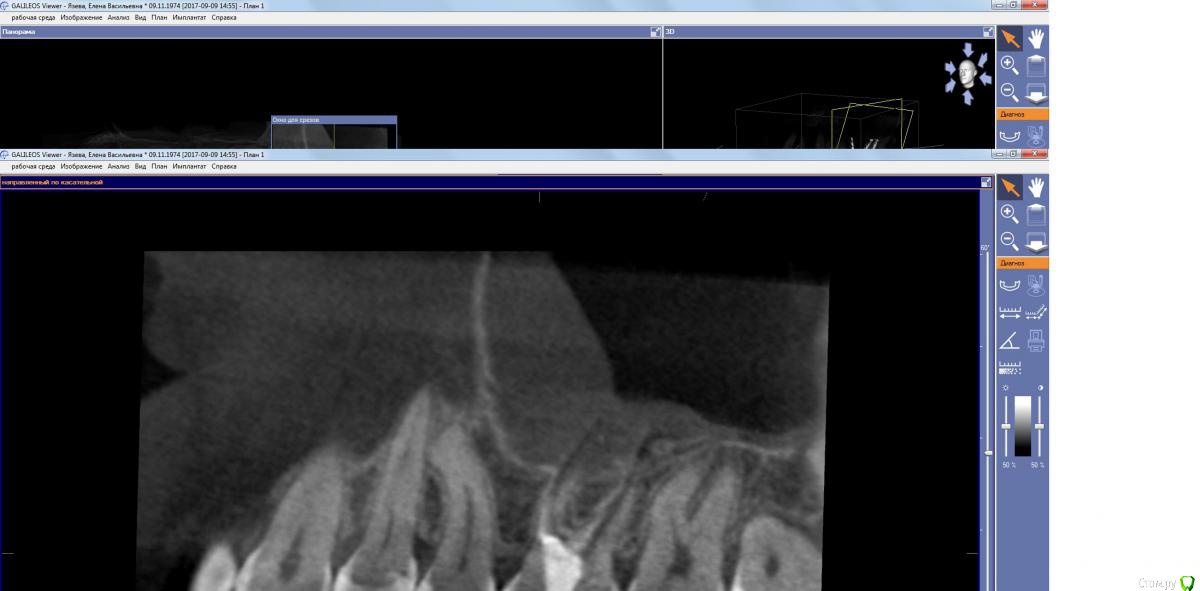

kamranchick Опубликовано 15 сентября, 2017 Поделиться Опубликовано 15 сентября, 2017 Господа, терапевт наш пролечил зуб, и болит пазуха уже месяц... сам зуб не болит, какой план действий? Ссылка на комментарий

kamranchick Опубликовано 15 сентября, 2017 Автор Поделиться Опубликовано 15 сентября, 2017 (изменено) Лор говорит хронический гайморит в стадии обострения, но провоцирует зуб, короче все как всегда... Изменено 15 сентября, 2017 пользователем kamranchick Ссылка на комментарий

parallax Опубликовано 16 сентября, 2017 Поделиться Опубликовано 16 сентября, 2017 Это пристеночно-гиперпластическая форма гайморита, застарелая хронь, которая появилась не вчера. Возможно, обострение спровоцировали паффы (куда ж без них). Я думаю, стоматологи тут не при чём. Хотя ЛОРики всегда обвиняют нас (скоро вменят убийство Кеннеди). В каналы лезть больше не надо, отправляйте в ЛОР отделение, лечение этого гайморита хирургическое. 1 Ссылка на комментарий